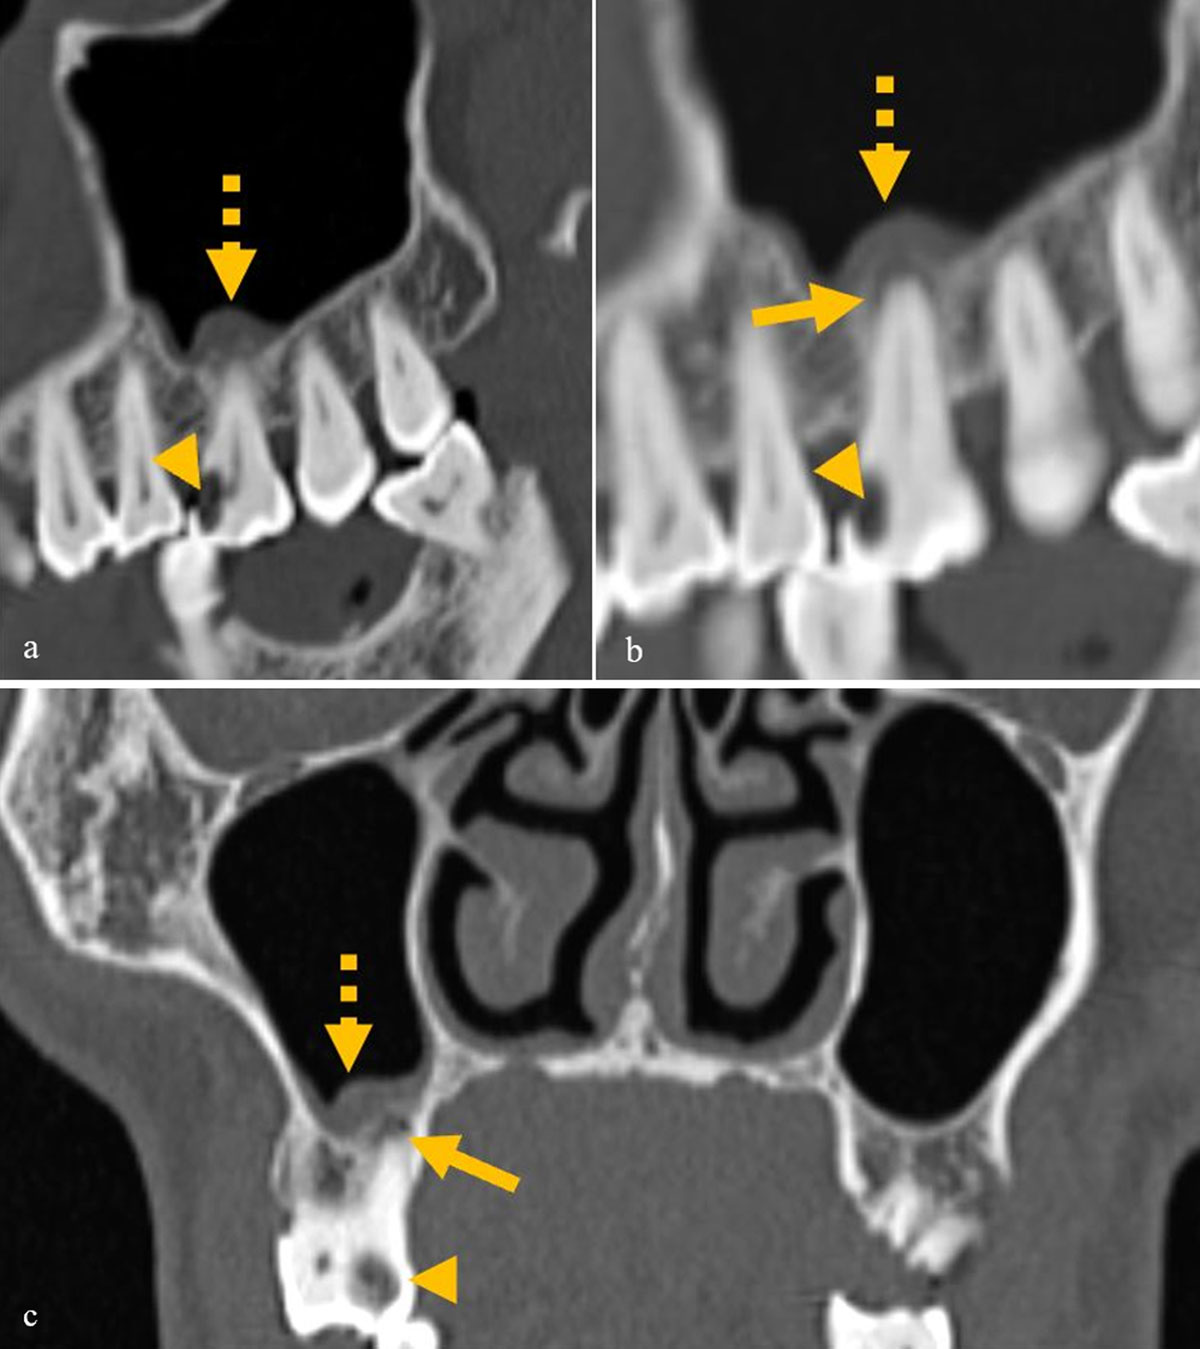

Figure 2

(a–c) A case of mild odontogenic sinusitis, showing dental caries (arrowhead) and mild periapical lucency (arrow) in the same tooth with mild mucosal thickening only adjacent to the diseased tooth (dashed arrow).

Figure 3

Images of two different patients showing dehiscence of the floor of the maxillary sinus (double lined arrow) and mucosal thickening and the causative diseased tooth with caries (arrowhead) and periapical lucency (arrow).